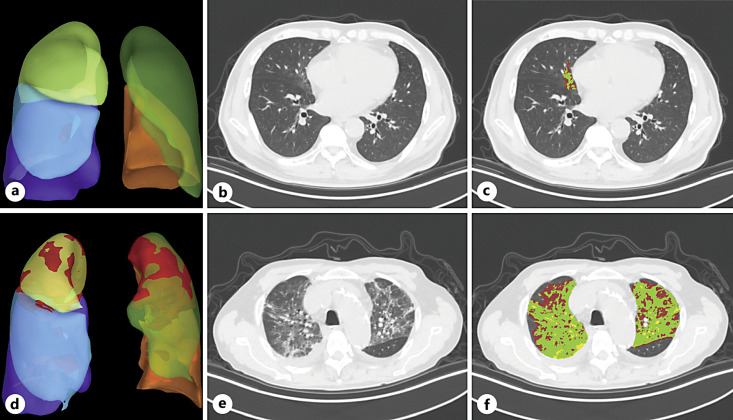

Methods: This was a two-center retrospective observational study of patients on hemodialysis diagnosed with COVID-19 at the Lingang and Xuhui campuses of Shanghai Sixth People's Hospital. Patients were randomized into the training (130) and validation cohorts (54), while 59 additional patients served as an independent external validation cohort. Artificial intelligence-based parameters of chest computed tomography (CT) were quantified, and a nomogram for patient outcomes at 14 and 28 days was created by screening quantitative CT measures, clinical data, and laboratory examination items, using univariate and multivariate Cox regression models.

Abstract Image